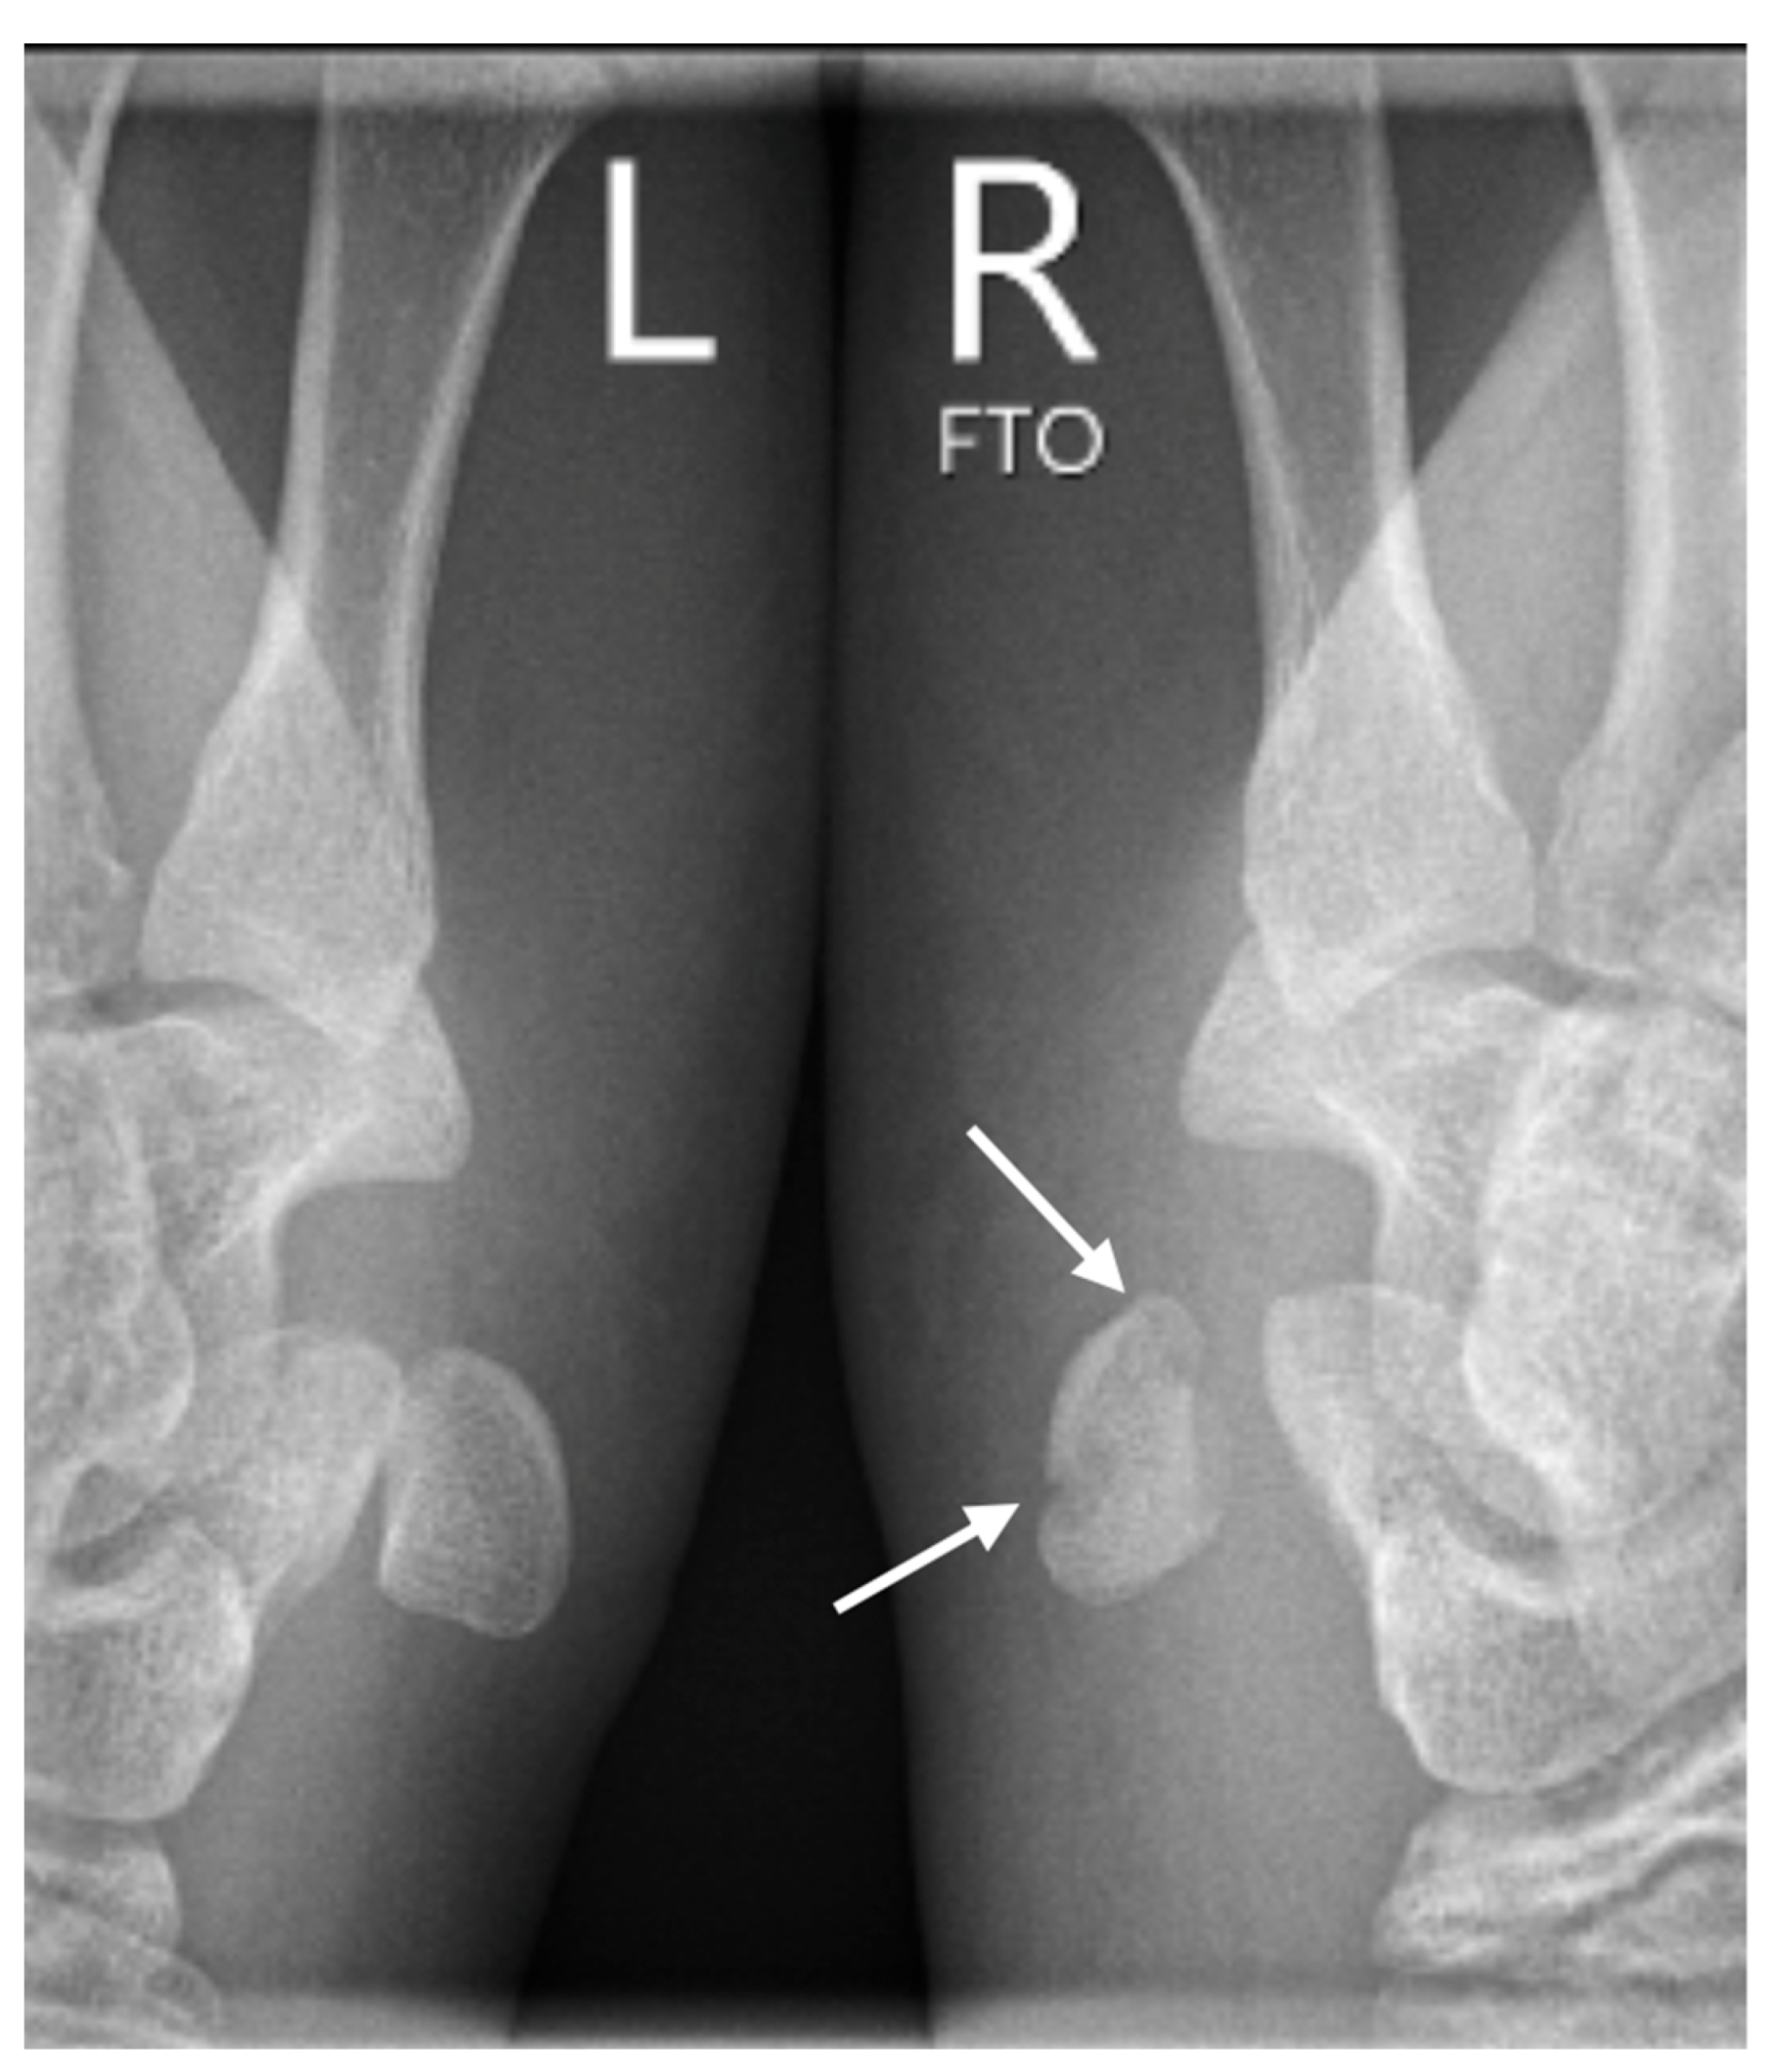

Further confirmation of the dislocation was obtained through subsequent conventional radiographs, specifically utilizing the semi-supination oblique view in a 30° angle (pisiform, pisotriquetral view), with side-by-side comparison of both wrists (Figure 3).

Figure 3.

The semisupination oblique X-ray in 30° angle, side-by-side comparison (L: left, R: right), showing a non-displaced fracture of the pisiform bone (white arrows).